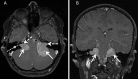

Methods: High resolution MRI was performed in children genetically proven to have NF2. The superior vestibular nerve (SVN) and inferior vestibular nerve (IVN) were visualised along their course with points of tumour origin calculated as a percentage relative to the length of the nerve.

Results: Out of 41 patients assessed, 7 patients had no identifiable eighth cranial nerve disease. In 16 patients there was complete filling of the internal auditory meatus by a tumour mass such that its specific neural origin could not be determined. In the remaining 18 cases, 86 discrete separate foci of tumour origin on the SVN or IVN could be identified including 23 tumours on the right SVN, 26 tumours on the right IVN, 18 tumours on the left SVN and 19 tumours on the left IVN.